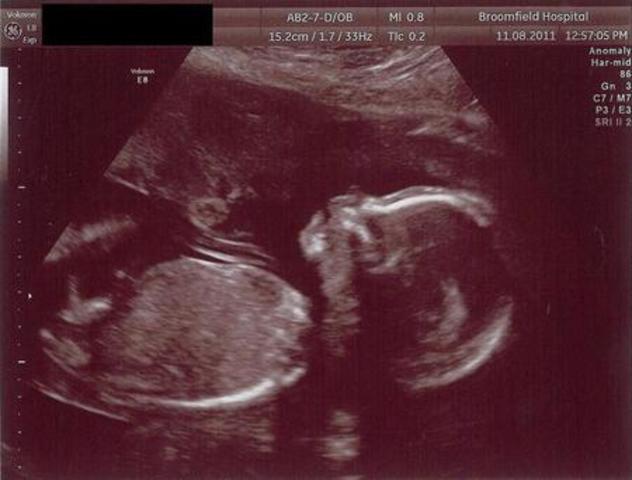

• 12 Semana de Gestación

12 Semana de Gestación

En los rasgos externos la cabeza está erecta, el cuello está casi recto y bien definido, también el oído externo adopta su forma y se ha desplazado casi a su posición definitiva en la cabeza

• Period: to

12 SDG

El saco vitelino se ha retraído, el feto deglute líquido amniótico y puede responder a la estimulación de la piel, los ovarios descienden por debajo del reborde pélvico, también se produce la hormona paratiroidea y la sangre se puede coagular